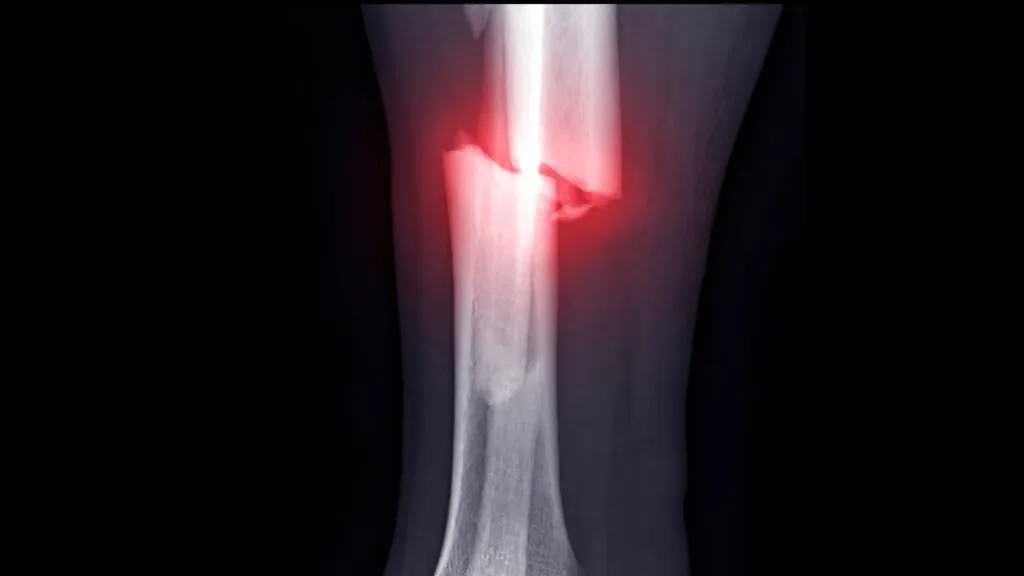

Para garantir seus direitos sobre as sequelas de fratura de tíbia e fíbula, você precisa de provas. Guarde todos os Raio-X (do dia da quebra e os atuais), relatórios médicos descrevendo a limitação de movimento e receitas de remédios para dor.